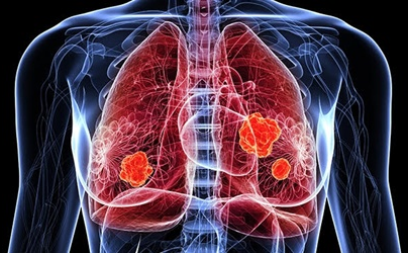

이번 기사에서는 폐암 초기 증상에 대해 자세히 정리해 알려 드리겠습니다 . 폐암은 국내암 사망률 1 위로, 과거에는 흡연이 폐암의 주된 원인 이었지만 , 현재는 비흡연 폐암 환자도 대폭 증가했습니다 . 폐암은 의학 기술로 발달하여 생존율이 높아지고 있습니다 . 폐암의 초기 증상은 무엇인가를 알아보겠습니다.

폐암의 초기 증상